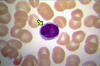

What cell is this?

Eosinophil of a horse